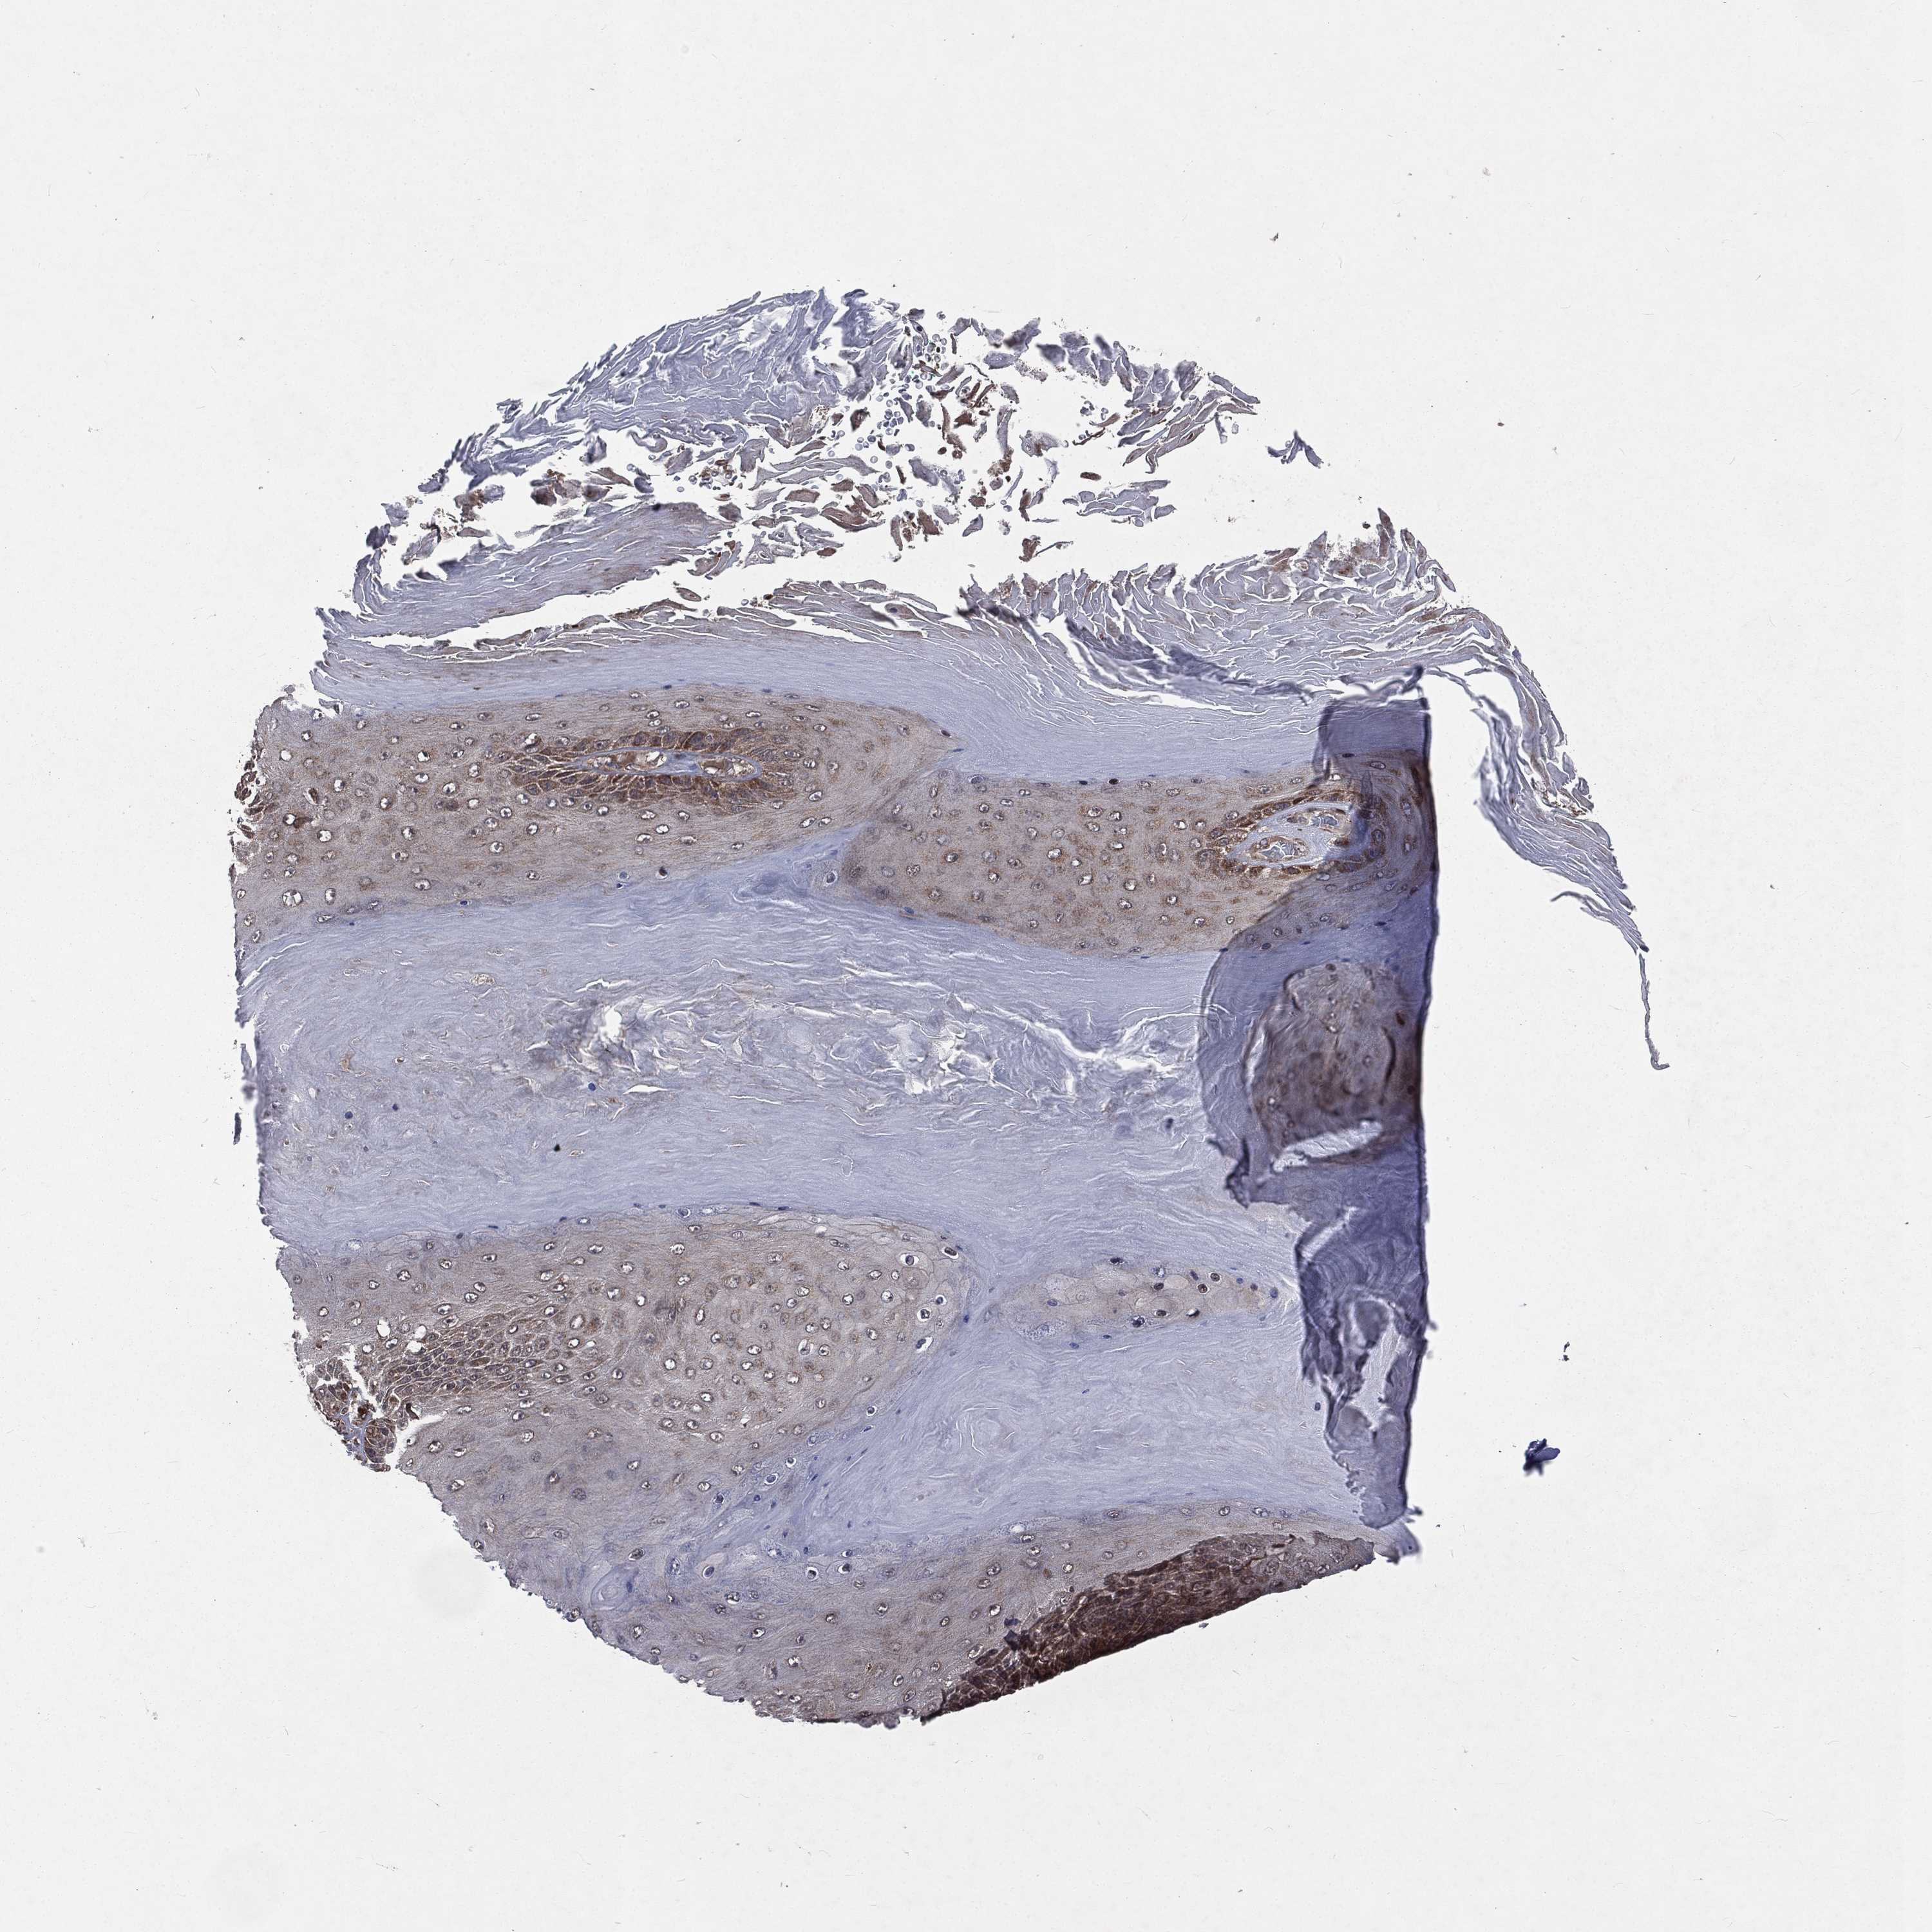

SKIN CANCER - Protein expressioni

A mouse-over function shows sample information and annotation data. Click on an image to view it in a full screen mode. Samples can be filtered based on level of antibody staining by selecting one or several of the following categories: high, medium, low and not detected. The assay and annotation is described here.

Antibody stainingi

Antibody staining in the annotated cell types in the current human tissue is reported as not detected, low, medium, or high, based on conventional immunohistochemistry profiling in selected tissues. This score is based on the combination of the staining intensity and fraction of stained cells.

Each image is clickable and will lead to virtual microscopy that enables deeper exploration of all samples and also displays staining intensity scores, fraction scores and subcellular localization as well as patient and tissue information for each sample.

Antibody HPA061571

Staining

High

Medium

Low

Not detected

Intensity

Strong

Moderate

Weak

Negative

Quantity

>75%

75%-25%

<25%

None

Location

Nuclear

Cytoplasmic/membranous

Cytoplasmic/membranous,nuclear

Squamous cell carcinoma, NOS

Basal cell carcinoma